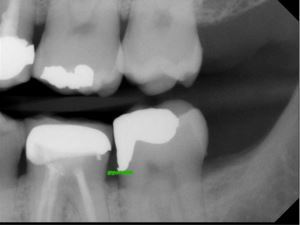

Typically, a post-op bitewing is taken to confirm the proper adaptation of restorative material to tooth structure, mainly when deep margin elevation is used to elevate a margin for indirect restorations. Deep margin elevation can be utilized near the bone with negligible effects on the biologic width when performed in a limited area.

In some cases, the matrix band may need to be adapted to accommodate the prep’s subgingival aspect. A #2 Tofflemire band or a modified #1 Tofflemire band can extend the matrix to ensure an adequate seal of the margin elevation material to the tooth.